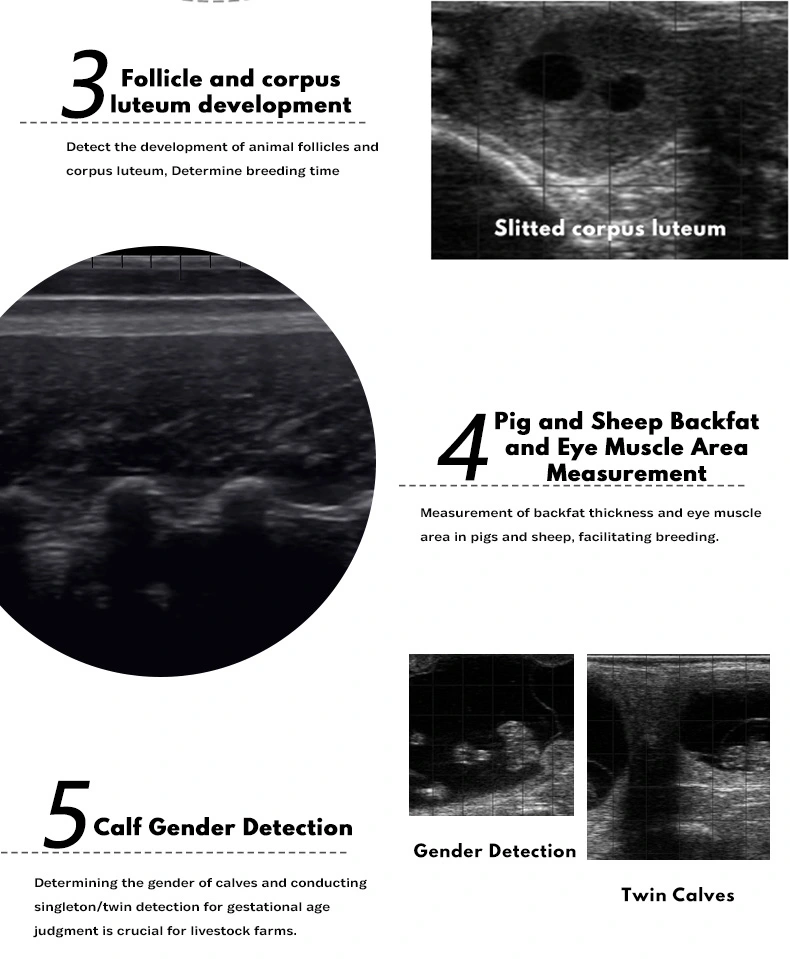

The BXL-V60 Video Glasses B-Ultrasound is a lightweight, durable veterinary diagnostic system featuring HD OLED 2D/3D switchable video glasses and an 8.0-inch LCD host display. With an IP56 waterproof design and over 7 hours of battery life, it’s ideal for fieldwork. The system supports a variety of probes, including rectal and backfat types, making it suitable for cattle, pigs, sheep, goats, horses, and more. It enables accurate pregnancy detection, backfat measurement, and organ analysis. The goggles offer a clear, immersive view for fast, comfortable, all-day scanning.